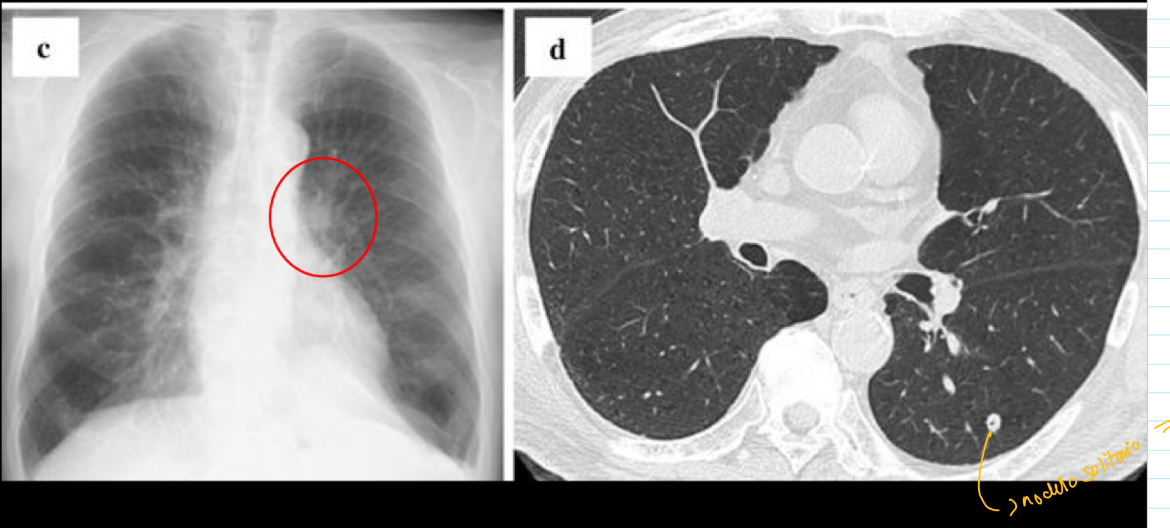

Que se ve en la primoinfecion

Nódulo solitario

si ves un nódulo solitario en q piensas

CÁNCER

que es y como sabes

Tb x nódulo de ghon